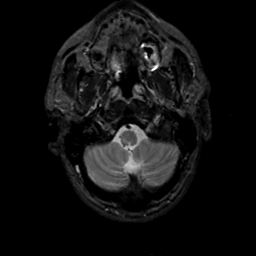

MR Study #14, June 2, 1991 -- Slice #5